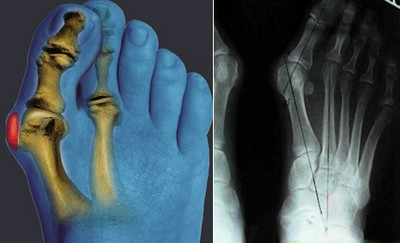

- Артродез (чаще всего выполняется при поражении мелких суставов пальцев рук или ног, а также при проблемах с голеностопом);